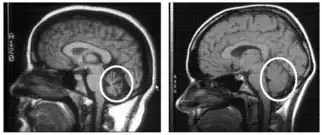

To select an appropriate and accurate diagnostic test for cerebellar degeneration, it is crucial that a range of factors specific to each patient are taken into consideration. These include; the patient's age, acuity of their signs and symptoms, associated neurological conditions, and family history of hereditary forms of cerebellar degeneration.[3] A diagnosis for cerebellar degeneration is regarded after any of the aforementioned signs and symptoms surface. For genetically classified forms of cerebellar degeneration, genetic testing can be carried out in order to confirm or deny the diagnosis, where this form of testing is only possible if the gene responsible for the cause of the condition is recognised.[24] In saying this, for most conditions the genetic cause of cerebellar degeneration is unidentified, hence these patients cannot proceed with genetic testing.[1] In cases where cerebellar degeneration is acquired, a diagnosis can be established using imaging methods such as computerised tomography (CT scans) and magnetic resonance imaging (MRI), necessary to detect brain abnormalities in patients with cerebellar degeneration.[25]